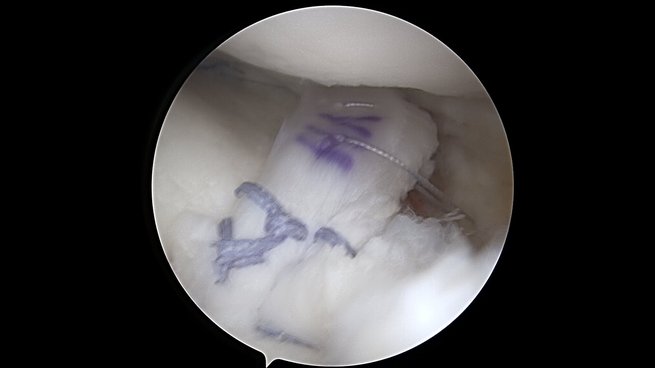

Meniskus

Der Meniskus fungiert als „Stoßdämpfer“ zwischen Oberschenkel und Unterschenkel, verbessert die Kongruenz der Gelenkpartner und trägt zusätzlich zur Stabilität des Kniegelenkes bei. Je nach Rissform, Patientenalter, traumatischer oder degenerativer Ursache bestehen unterschiedliche Behandlungsoptionen von konservativer Therapie bis hin zur operativen Versorgung mittels Teilresektion oder Meniskusnaht. Bei speziellen Meniskusverletzungen (z.B. der sogenannten Wurzel-Läsion) kann – um den Einheilungsprozess zu gewährleisten – auch ein Zusatzeingriff wie eine Umstellungsosteotomie bei O-Beinen nötig werden.

Bei jungen Patienten mit Meniskusverlust besteht auch die Möglichkeit einer sog. Meniskustransplantation, um langfristig das Fortschreiten der Arthrose hinauszuzögern. Hierbei wird aus einer Spenderbank ein bzgl. Größe und Form passender Spendermeniskus ausgewählt und nach Entfernung des defekten Eigenmeniskus im Gelenk fixiert.